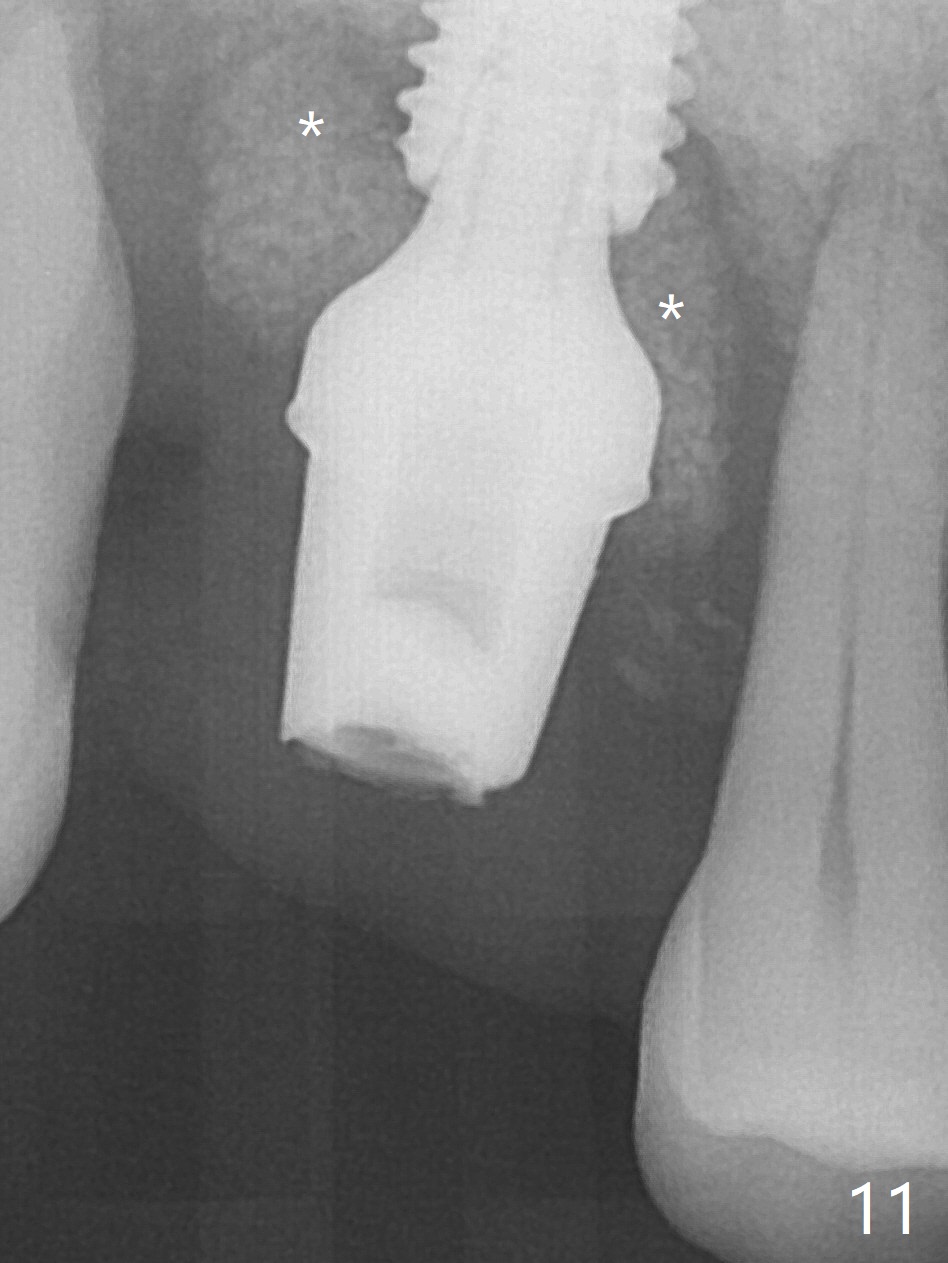

Initial osteotomy depth is 4 mm (Fig.7). The sinus membrane is found to be perforated when the depth increases to 8 mm. The latter could be prevented by taking CT and/or using osteotome. The subsequent osteotomy depth is 5 mm until 4.0 mm in diameter. When the 4.5 mm tap is inserted with initial stability, the shortest implant (8.5 mm, Fig.8 green) will be partially protruded into the sinus and partially exposed in the socket and the cuff of the abutment is expected to be around 6 mm (pink). Since the 5 mm tap achieves primary stability, a 5x8.5 mm implant (following placement of Osteogen plug to repair the perforated sinus membrane) is placed at the level just mentioned (Fig.9). Vanilla Graft mixed with minimal autogenous bone is packed (Fig.10.11 *) before and after insertion of a 6.5x5(4) mm abutment. An immediate provisional as well as a piece of Osteogen plug is fabricated to close the socket gap. The provisional and the abutment are dislodged 1 month postop (Fig.12). The wound has healed. The abutment is reloaded without the provisional. The implant appears to osteointegrate 4.5 months postop (Fig.13); in addition the bone graft seems to have migrated toward the roots of the neighboring teeth (arrows).